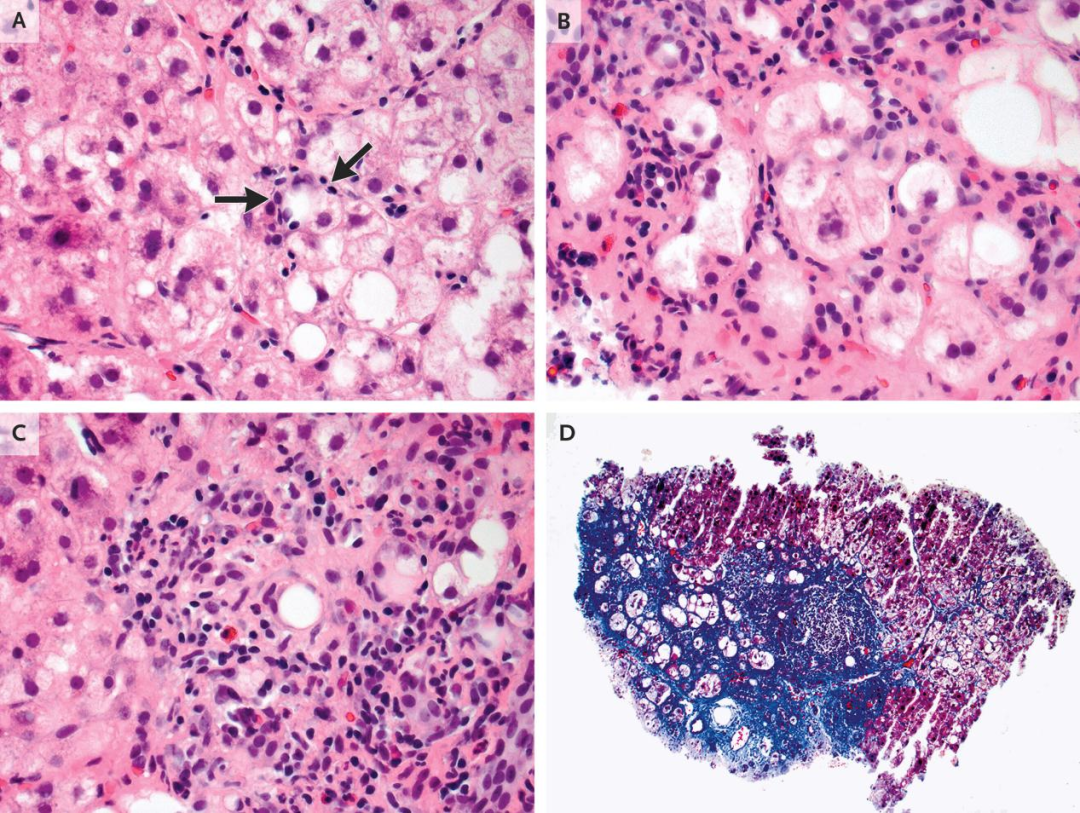

4.病理讨论Mino-Kenudson医生介绍,移植肝病理检查(图2)显示背景实质主要为微结节性肝硬化。尽管大多数肝硬化结节无脂肪变,少数结节见脂肪变和以肝细胞气球样变为特征的脂肪性肝炎。移植肝右叶见三处病变。两处因射频消融完全坏死,第三处见存活肝细胞癌证据,主瘤和卫星结节呈腺泡状或小梁状生长模式(或二者兼具),肿瘤细胞核质比远高于正常肝细胞。一卫星结节部分围以肌壁,提示血管侵犯后肿瘤在门脉系统内膨胀性生长。这些表现符合脂肪性肝炎背景下微结节性肝硬化发生的肝细胞癌。基于血管侵犯,肿瘤确定为病理分期2期。

图2. 肝脏外植体标本